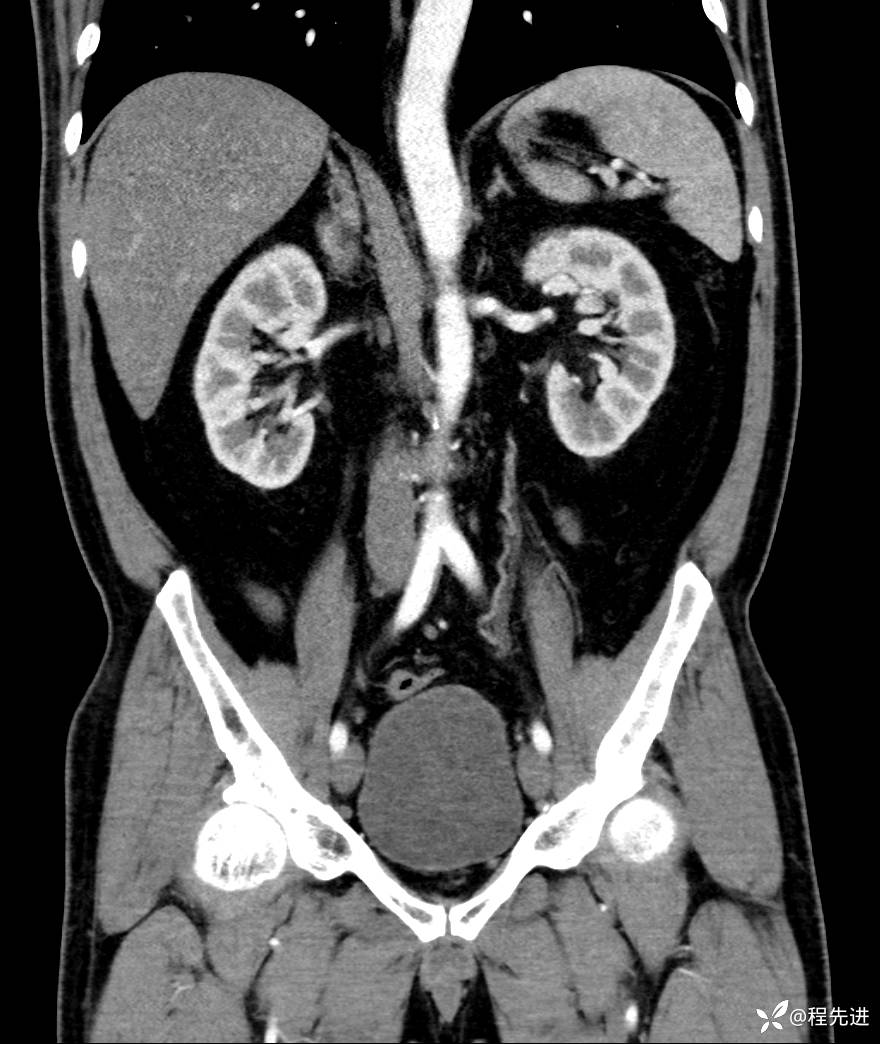

【腹盆】特别精彩病例|发现腹膜后肿物1月余

患者性别:男

患者年龄:42岁

主诉:发现腹膜后肿物1月余

现病史:患者1月余前查体,行超声检查提示:后腹膜囊实性肿块;慢性胆囊炎伴胆囊内结石;无腹痛腹胀,不伴腹泻发热等;偶感腰背部酸痛。

CT平扫+增强: